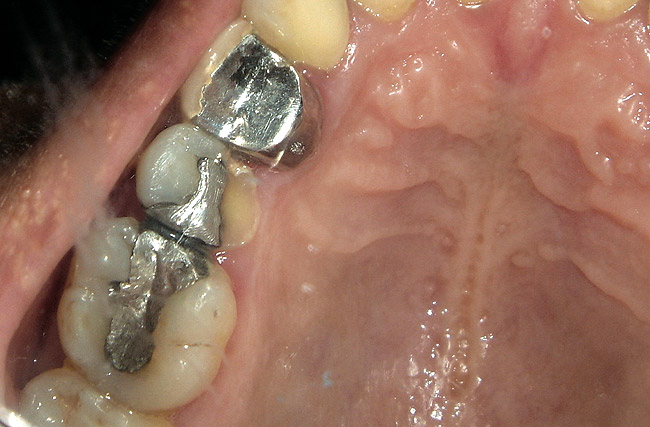

Figure 7  defective amalgam restoration with fractured cusp restored with packable RBC

Figure 7

The search for an ideal direct esthetic restorative material is still ongoing. Among the array of RBC materials, some are readily available in the market (flowable, packable, and fiber-reinforced), others have just recently been introduced (siloranes-based), and a few are still in development phase (fluoride-releasing). Individual properties of different RBC materials define their advantages, disadvantages, and clinical uses. Each type of RBC material has its own virtues in some clinical aspects and shortcomings in other aspects. Every material possesses either one or the other ideal properties of a restorative material, but not all of them. Therefore, it is important for a clinician to use every material judiciously and for a clinical application for which it is best suited (Figure 5, Figure 6, Figure 7, Figure 8, Figure 9 and Figure 10).